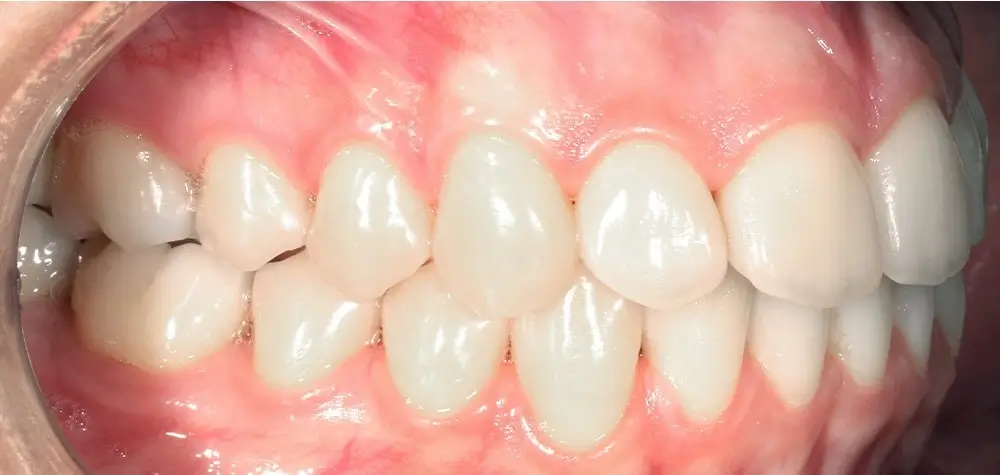

Открытый прикус - Кейс 6

Эффективность устранения дефекта прикуса посредством элайнеров FlexiLigner.

Результаты лечения